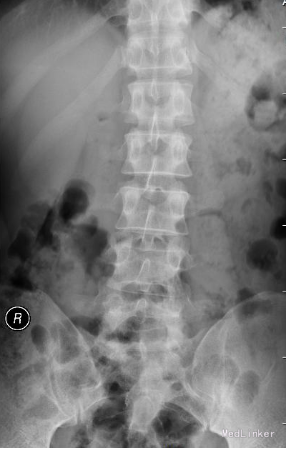

35岁 男性 主诉:反复右下肢放射性疼痛麻木8个月,加重3天

生命体征平稳,痛苦表情, 专科查体: 右下肢强迫性屈髋屈膝位; L5/S1棘突间及右侧椎旁压痛,并向右下肢放射; 右小腿后侧及足背外侧皮肤感觉减弱; 右足拇跖屈肌力3级; 右侧直腿抬高试验5°(+), 右侧跟腱反射消失。 入院三大常规,生化指标等均正常范围

诊断:腰椎间盘突出症 (腰5/骶1髓核游离型) VAS评分:9分 ODI评分:96% 疼痛剧烈,右下肢难以伸直,坐卧不宁;给予常规脱水,激素,止痛等治疗无效;不同意手术,反复要求保守治疗。 保守治疗3天,患者疼痛仍无明显缓解,同意行手术治疗 手术方案:椎板间隙入路PELD 术后予以止痛,脱水,小剂量激素等治疗, 术后第二天:右下肢麻木疼痛明显缓解。查体:右小腿后侧及足背外侧皮肤触觉恢复;右足拇跖屈肌力4+级;右侧直腿抬高试验(-);右侧跟腱反射仍减弱。 术后第5天:出现右小腿及足底针刺样疼痛症状加重,麻木感,伴有右下肢间歇性抽搐,次数较频繁,以夜间为甚。查体:腰椎活动无明显受限,右小腿后面及右足背外侧触痛明显;双下肢屈伸肌力、肌张力基本正常;右侧直腿抬高试验(-),右侧跟腱反射仍减弱。 予以加大NSAID及地米治疗,效果不明显,夜间疼痛难以入睡。复查腰椎MRI,未见髓核再脱出,减压彻底 诊断:考虑右侧骶1神经根神经病理性疼痛 治疗: 普瑞巴林 75mg Bid;神经妥乐平 2# Bid; 阿米替林 25mg Bid 外加神经营养治疗 治疗1周后,症状明显缓解